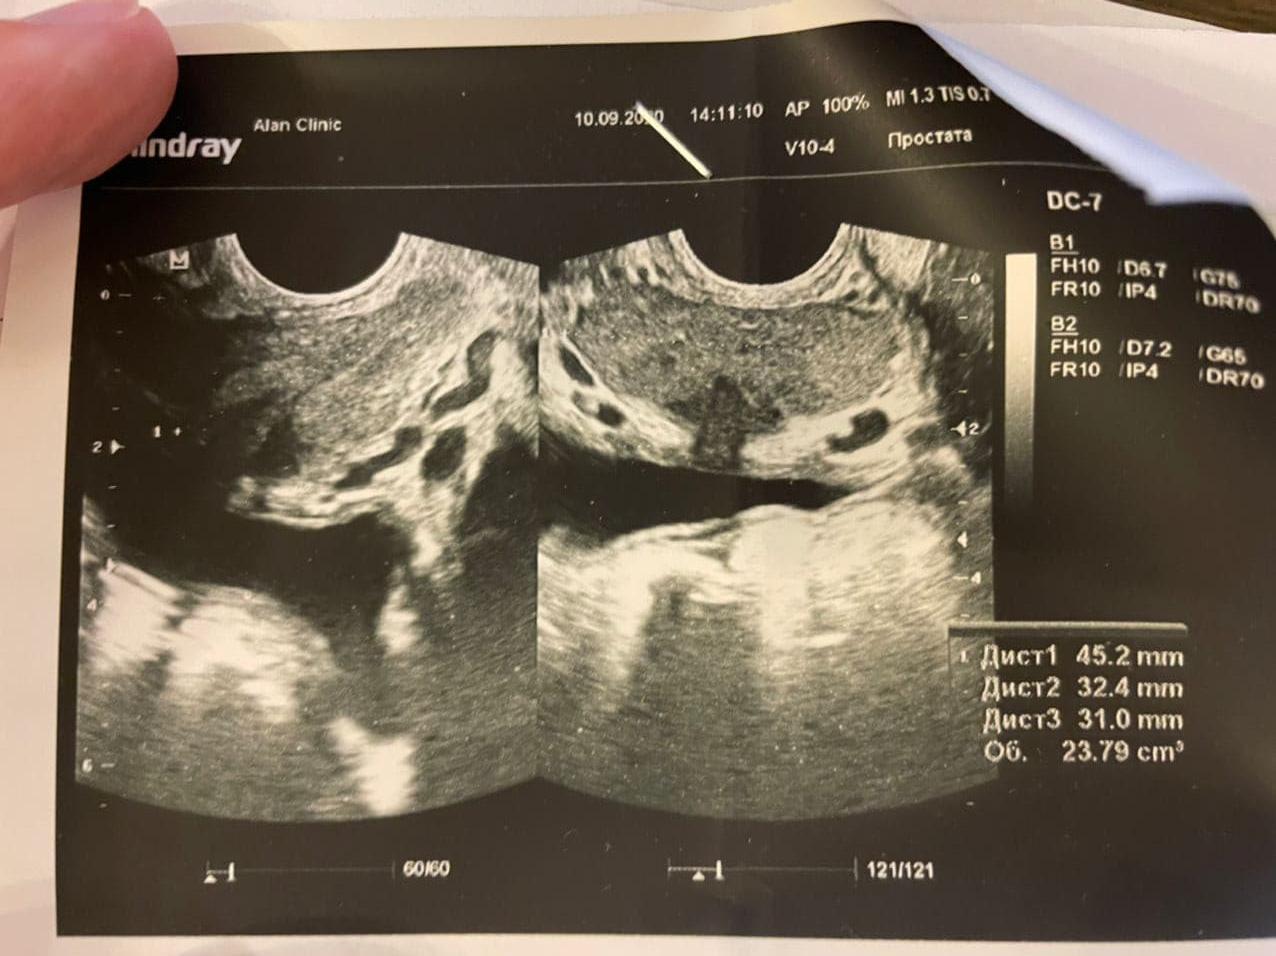

Левофлоксацин 500мг 10 таблеток

Все принимал, попутно сдав анализы на кровь, мочу и сделал ТРУЗИ (Приложил картинками). Уретра все это время остаётся опухшей, плюс я не знал, что мне нужно принимать пребиотики и у меня 4 дня в этом курсе была диарея, да ещё и под индометацином, который драл меня изнутри.

Я пришел меня посмотрели и посмотрели простату, взял сок и сказали по анализам, что "Нет у меня простатита". (Анализы в картинках). Все картинки будут идти по очереди и назначили курс лечения "Неспецифического уретрита". (картинка лечения прикреплена).